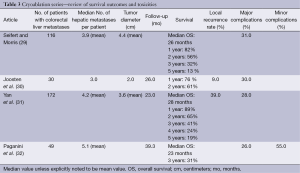

Cryoablation is performed through the use of a probe within the lesion, where argon is infused, dropping tissue temperatures to –40 degrees centigrade and creating an ice ball of various sizes depending on probe configuration. Within the ice ball there are predictable thermal zones ranging from –40 degrees to 0 degrees centigrade. Tissue death occurs at –20 to –40 degrees centigrade. Advantages of cryoablation include ability to visualize the ice ball while using CT guidance and less procedure related pain. There are variable survival rates and high rates of complications (7). Disadvantages include the need for multiple probes and lack of a coagulative effect potentially leading to bleeding complications (28). The high rate of complications and fear of cryoshock has led to this technique falling out of favour as other safer and equally effective techniques have evolved (7). Currently cryoablation has been replaced by RFA and microwave ablation for ablative treatment within the liver (Table 3).